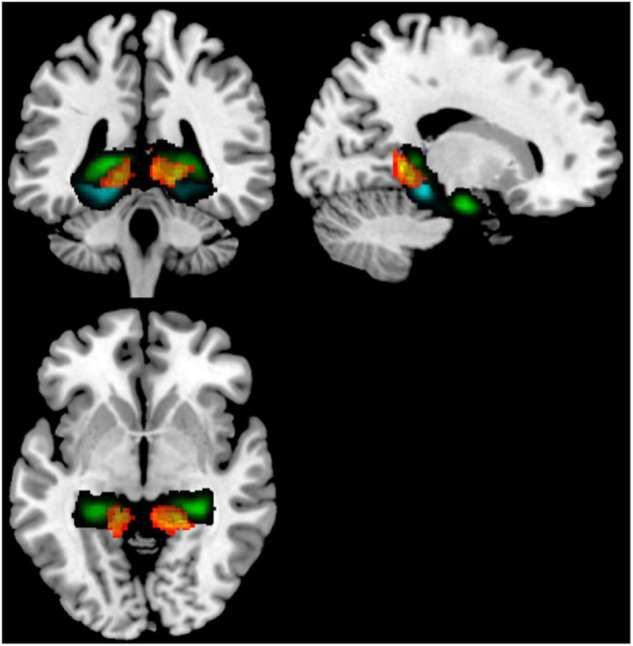

Because cerebellar lobules IV/V had such consistent altered rsFC across hippocampal and parahippocampal subregions in our comparison of younger non-users to older non-users, to determine specificity, we next performed a seed-to-voxel analysis contrasting older users to older non-users, using bilateral cerebellar lobules IV/V as seeds. This analysis revealed two fairly symmetric clusters of target voxels from these seeds, indicating stronger rsFC in younger vs. older non-users. These clusters were bilateral (x = –14, y = –50, z = 10; x = +12, y = –44, z = +02) and encompassed posterior cingulate cortex, lingual gyrus, hippocampus, and pPaHC (Figure 3 and Table 4).

TABLE 4: Composition of significant clusters in a seed-to-voxel analysis comparing aged users vs. aged non-users, using bilateral cerebellar lobules IV/V as seeds.

| Coordinates | Total voxels | p-FWE |

| (–14, –50, +10) | 664 | 0.0039 |

| Number of voxels | Percent coverage | Region |

| 149 | 3 | Precuneous |

| 85 | 4 | Posterior cingulate |

| 84 | 6 | Lingal gyrus, L |

| 80 | 21 | posterior parahippocampal gyrus, L |

| 36 | 4 | Cerebellum lobes IV/V, L |

| 23 | 3 | Hippocampus, L |

| Cluster 2 | ||

| Coordinates | Total voxels | p-FWE |

| (+12, –44, +02) | 444 | 0.038 |

| Number of voxels | Percent coverage | Region |

| 125 | 5 | Posterior cingulate |

| 99 | 6 | Lingual gyrus, R |

| 25 | 4 | Vermis IV/V |

| 19 | 6 | posterior parahippocampal gyrus, R |

| 17 | 2 | Hippocampus, R |

| 15 | 2 | Cerebellum lobules IV/V, R |

| 12 | 5 | Vermis III |

| 6 | 3 | Cerebellum lobule III R |

Coordinates are (x, y, z). Regions with 1% coverage or greater are reported.